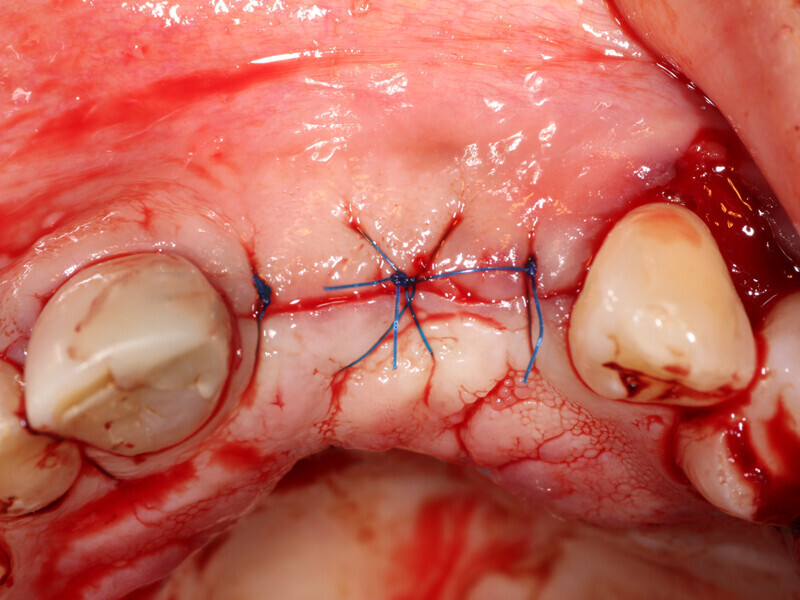

Fig. 14: Flap is closed without tension using 5-0 Polypropylene suture (Riverpro, Osteolife Biomedical, Jupiter, Fla.) in a simple interrupted pattern.